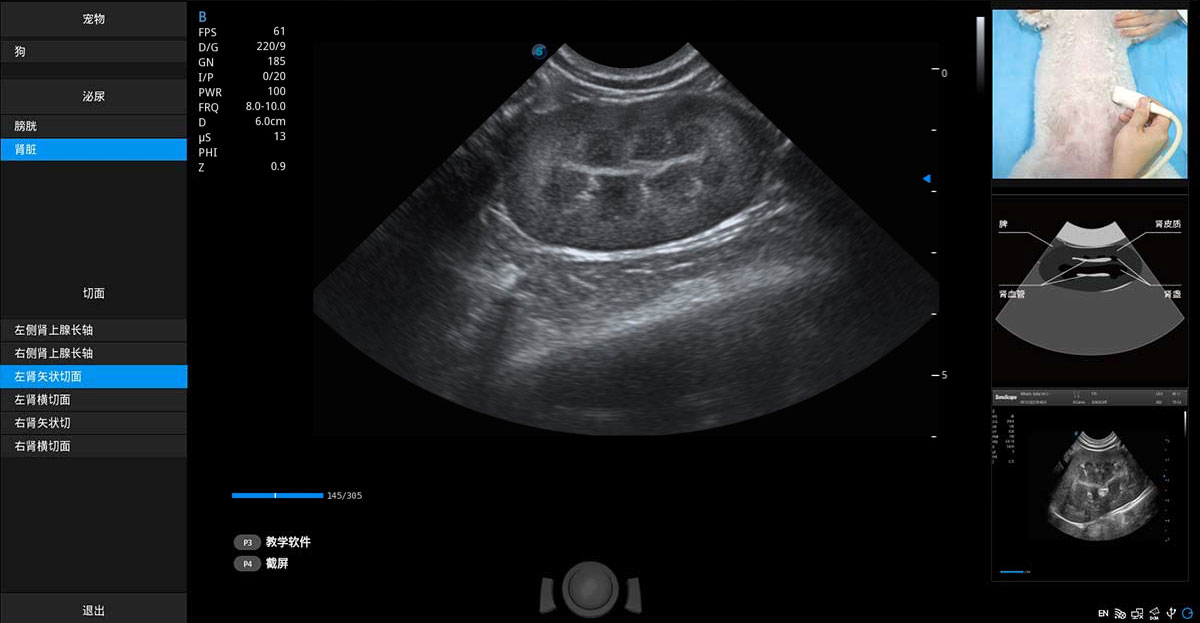

提供解剖示意圖、標(biāo)準(zhǔn)超聲圖像、掃查手法涂和操作者實(shí)時(shí)檢查圖像,指導(dǎo)操作者進(jìn)行標(biāo)準(zhǔn)切面的正確掃查。

ProPet 80 專為動(dòng)物醫(yī)生設(shè)計(jì),對(duì)不同的動(dòng)物體型和生理結(jié)構(gòu)作出了針對(duì)性的優(yōu)化。通過(guò)動(dòng)物影像專用軟件,可滿足個(gè)性化的應(yīng)用需求,幫助動(dòng)物醫(yī)生獲得更精確的診斷數(shù)據(jù)。